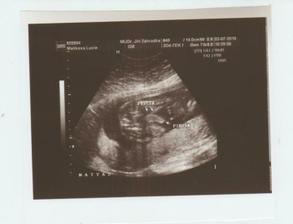

Konečně 26.1. 2010 přišla menstruace a mohla jsem si začít píchat injekce Gonal do břicha (nebolí to) a po 4 dnech kontrolní ultrazvuk, kolik se tvoří vajíček, zatím dobrý na ultrazvuku mý vaječníky začaly připomínat shluk žabých miminek na louži (snad jste to některá z vás někdy viděla, jinak to byla blbá poznámka). Ještě týden injekcí a 10.2. 2010 jsme já i manžel objednaní na osmou ráno opět do Pronatalu, já na odebrání vajíček a manžel na odběr spermatu. V jedenáct jsem šla na řadu, malé množství narkozky a za pět minut jsem to měla za sebou, celkem 6 použitelných vajíček připravené k oplodnění. Každý den jsme si mohli zavolat, jak se naše miminka vyvýjejí a po 5ti dnech byla dvě statečná embrya z šesti připravená na transfer zpět do dělohy. 15.2.2010 byla jedna hodina odpoledne a já pod ultrazvukem sledovala, jak moji drobečci putují zpět do svého domečku, kde se o ně budu 9 měsíců starat. A teď jen čekat, jestli se dostaví menstruace a jinak za dva týdny na krevní testy.